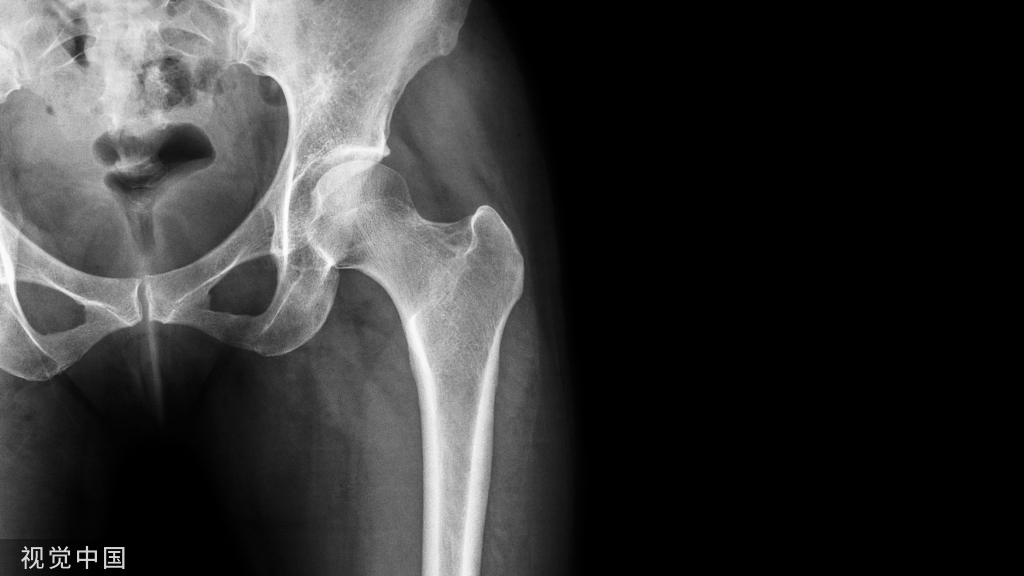

开放性骨折是创伤骨科治疗的难点,治疗效果取决于伤情严重程度、治疗方案,以及手术操作和护理。今天我们就来学习一下

目前最常用的开放性骨折分型是Gustillo-Anderson 分型: Ⅰ型为低能量损伤,软组织损伤及伤口污染轻微,伤口长度通常<1 cm; Ⅱ型多为低能量损伤,但伤口长度≥1 cm,不合并广泛的软组织损伤、脱套、皮瓣及撕脱; Ⅲ型为高能量损伤,分为3个亚型:

• ⅢA型尚有足够软组织覆盖骨折端;

• ⅢB型存在骨膜撕脱、骨折端外露,污染较重,软组织不能覆盖骨折端且需要软组织重建手术覆盖骨折端;

• ⅢC型存在动脉血管损伤,需要行血运重建手术。Gustillo-Anderson分型利于医师选择手术方案,并指导预后,是目前广泛用于开放性骨折的分型系统,同时利于学术交流。